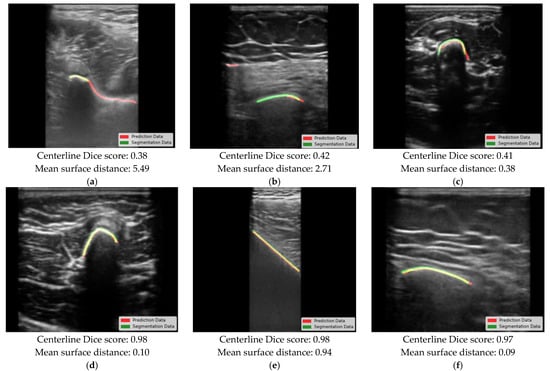

| Model | Centerline Dice Score (Mean ± SD) | Mean Surface Distance (Mean ± SD), Direction of Segmentation [mm] | Computation Time Per Million Pixels | ||||

|---|---|---|---|---|---|---|---|

| All Ages | <10 Years | >10 Years | All Ages [mm] | <10 Years [mm] | >10 Years [mm] | All Ages [ms] | |

| 1 | 0.80 ± 0.15 | 0.77 ± 0.17 | 0.83 ± 0.12 | 0.86 ± 1.04, 0.00 | 0.93 ± 1.35, −0.17 | 0.77 ± 0.69, +0.13 | 1.21 |

| 2 | 0.81 ± 0.14 | 0.78 ± 0.17 | 0.84 ± 0.10 | 0.82 ± 1.00, +0.07 | 0.98 ± 1.37, −0.07 | 0.69 ± 0.52, +0.18 | 0.79 |

| 3 | 0.82 ± 0.14 | 0.79 ± 0.17 | 0.84 ± 0.11 | 0.91 ± 1.08, +0.11 | 1.09 ± 1.46, +0.05 | 0.77 ± 0.61, +0.16 | 0.84 |

| 4 | 0.84 ± 0.14 | 0.81 ± 0.17 | 0.86 ± 0.10 | 0.48 ± 1.30, +0.21 | 0.74 ± 1.89, +0.19 | 0.28 ± 0.33, +0.21 | 1.12 |

| 5 | 0.84 ± 0.14 | 0.83 ± 0.16 | 0.85 ± 0.11 | 0.51 ± 0.93, +0.07 | 0.65 ± 1.23, +0.09 | 0.40 ± 0.48, +0.05 | 0.85 |

| Weighted model | 0.85 ± 0.13 | 0.82 ± 0.16 | 0.87 ± 0.09 | 0.78 ± 1.15, +0.05 | 1.0 ± 1.63, +0.07 | 0.61 ± 0.46, +0.03 | Not specified |